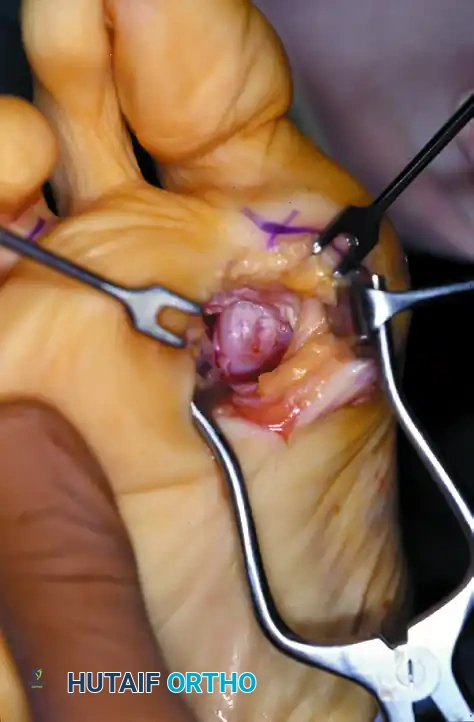

Adductor Tendon and Lateral Capsular Release

The lateral release is the biomechanical heart of the Modified McBride procedure. It mobilizes the tethered lateral structures, allowing the sesamoid apparatus to reduce beneath the metatarsal head.

- Begin the second stage with a dorsal longitudinal incision. Start 2 to 3 mm proximal to the dorsal aspect of the first web space to avoid postoperative web contracture. Extend the incision proximally between the first and second metatarsal heads for 3 to 4 cm.

- This approach provides adequate exposure of the adductor hallucis insertion into the base of the proximal phalanx, the lateral head of the flexor hallucis brevis (FHB) muscle converging on the fibular sesamoid, and the entire lateral capsule.

- Delicate retraction of the skin exposes the dorsal digital branches of the veins, which should be cauterized. Be highly vigilant for the terminal branches of the first dorsal intermetatarsal artery, which may be encountered adjacent to the proper digital branches of the deep peroneal nerve supplying the first web space.

- The main portion of the adductor tendon inserts into the base of the proximal phalanx just plantar to the longitudinal axis of the phalanx. It also possesses a smaller insertion, confluent with the lateral head of the FHB, into the fibular sesamoid.

Surgical Technique Tip: To easily identify the insertion of the adductor hallucis tendon, place a small, pointed, curved hemostat on the dorsolateral base of the proximal phalanx. Slide it firmly plantarward, then lift the hemostat dorsally and laterally. The tip of the instrument will reliably rest in the axilla of the adductor tendon insertion.

- Once the primary insertion is released from the proximal phalanx, grasp the tendon with a hemostat. Apply traction and displace it dorsally and laterally toward the second metatarsal.

- Spread the first and second metatarsal heads using a small Inge retractor or a Weitlaner retractor. Holding the adductor tendon under tension greatly facilitates deep exposure. The lateral head of the FHB, the lateral border of the fibular sesamoid, and the conjoined slip of the adductor tendon will come into clear view.

- Sever all attachments of the adductor into its conjoined insertion with the lateral head of the FHB into the fibular sesamoid. When fully released, traction on the adductor should result in free, independent movement without tethering the fibular sesamoid.

- Next, address the deep transverse intermetatarsal ligament, which lies just plantar to the adductor. Release this ligament carefully.

- Critical Pitfall: Release of the deep transverse metatarsal ligament severely endangers the neurovascular bundle to the first web space, which lies immediately beneath it. Slide a small Freer elevator between the ligament and the neurovascular bundle to protect these structures before incising the ligament. Following this, complete the lateral capsulotomy.